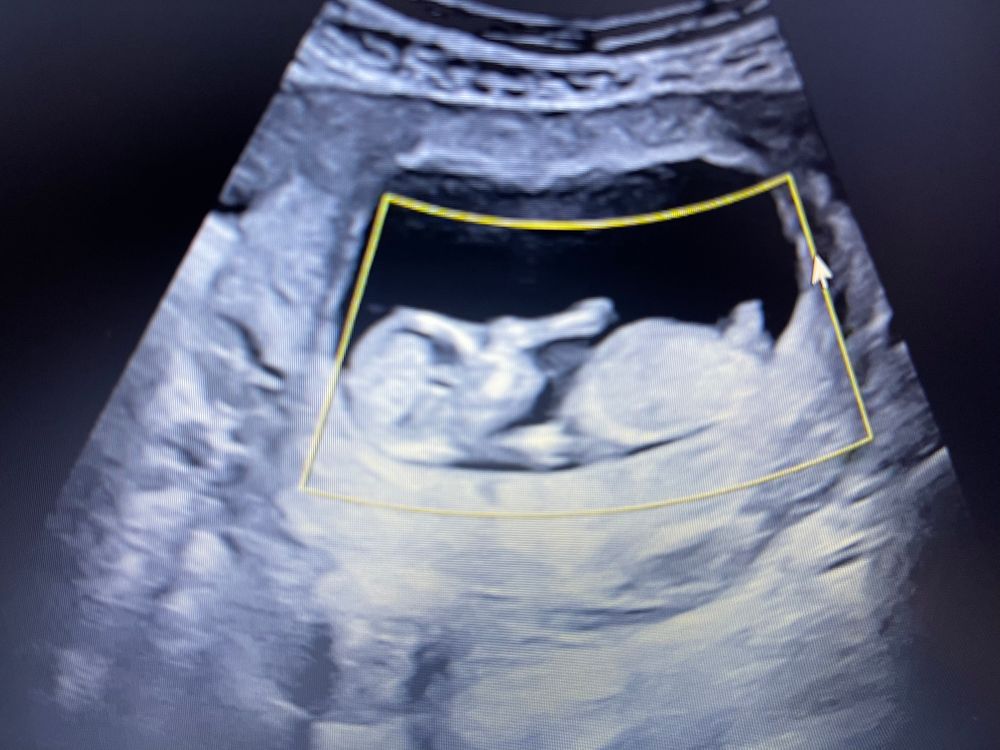

Половой бугорок на сроке 12 недель

УЗИ, КТГ, доплерДевочки, кто разбирается в половых бугорках, кого видите-мальчика или девочку?) врач узист ничего не ответила 🤷♀️

Девушки,пишу спустя время)))тот кто писал,что это мальчик оказались правы 😁🍾

Девочки определите тоже кто у меня ?